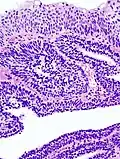

Micrograph of an inverted papilloma of the urinary bladder; H&E stained | |

An inverted papilloma, also known as Ringertz tumor,[1] is a type of tumor in which surface epithelial cells grow downward into the underlying supportive tissue. It may occur in the nose and/or sinuses or in the urinary tract (bladder, renal pelvis, ureter, urethra). When it occurs in the nose or sinuses, it may cause symptoms similar to those caused by sinusitis, such as nasal congestion. When it occurs in the urinary tract, it may cause blood in the urine.